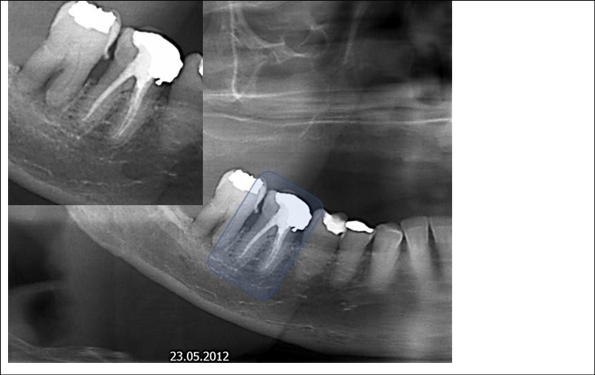

Figure 4 Periapical radiography of the molars and lower premolars region D. There is a fixed prosthesis with three elements, teeth 45 and 47 being pillars. Suspended element 46. Note the lack of material in the distal of tooth 45 and the excess in the mesial of the tooth 47, which characterize iatrogeny. Both teeth are treated endodontically. The endodontic treatment of teeth 44 and 45 is correct, apparently.

Figure 5 Periapical radiography of the molars and lower premolars region D. The dotted oval areas identify endodontic treatments for tooth roots 46. There is a prosthetic fused metal core to support the metallic crown on that same tooth. See that the root fillings are below the apical limit, and this characterizes iatrogeny. There is an apical radiolucent image, which may mean repair.